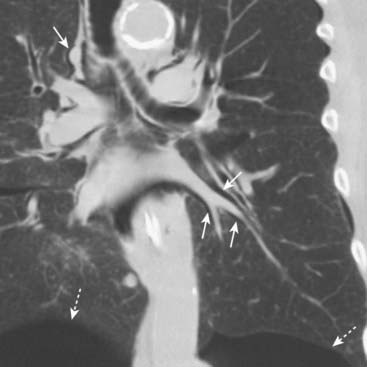

image

Figure 8-12 Pulmonary interstitial emphysema.

This coronal reformatted CT scan of the chest demonstrates air (solid white arrows) surrounding the pulmonary arteries (white branching structures) in the lung. This air arose from a ruptured alveolus in a patient with asthma and is tracking back to the hilum where it also produced pneumomediastinum and subcutaneous emphysema. The patient also has bilateral, basilar pneumothoraces (dotted white arrows).